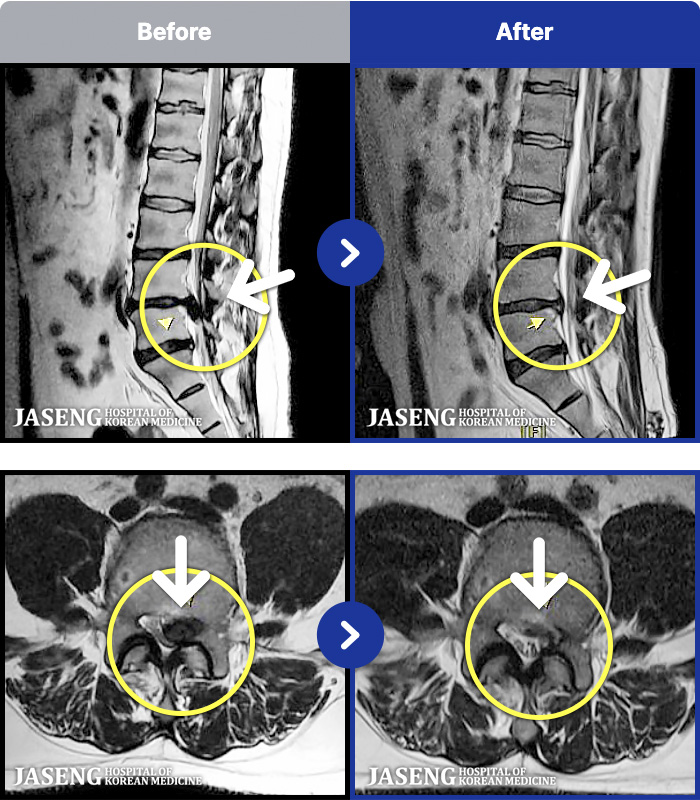

1,257 MRI ũ ʸ Ȯϼ.